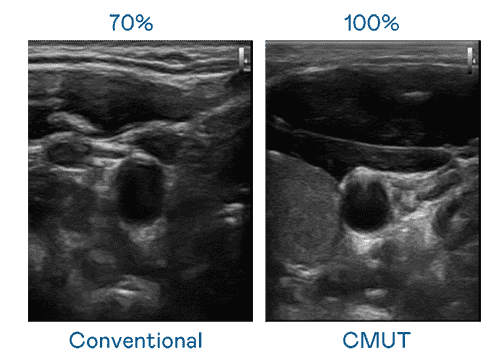

CMUT 技术是一种用电容式微机电元件来产生超音波讯号的技术。。与传统 PZT 压电式技术相比,,,,CMUT 频宽增加 30%,,更宽频的超音波讯号让影像解析度大幅提升,,,,是实现高影像品质医疗超音波扫描、、促进精准医疗发展的关键技术。。。。

大频宽带来超清晰影像

超音波影像的解析度高低,,首先取决于探头能发出的讯号频宽。。菠菜论坛 CMUT 可提供高清晰的超音波讯号,,,提供高频宽、、高灵敏度、、、影像纹理细节更高的超音波影像,,协助医护人员缩短影像判读时间及利用精准的医疗影像进行诊断。。。。